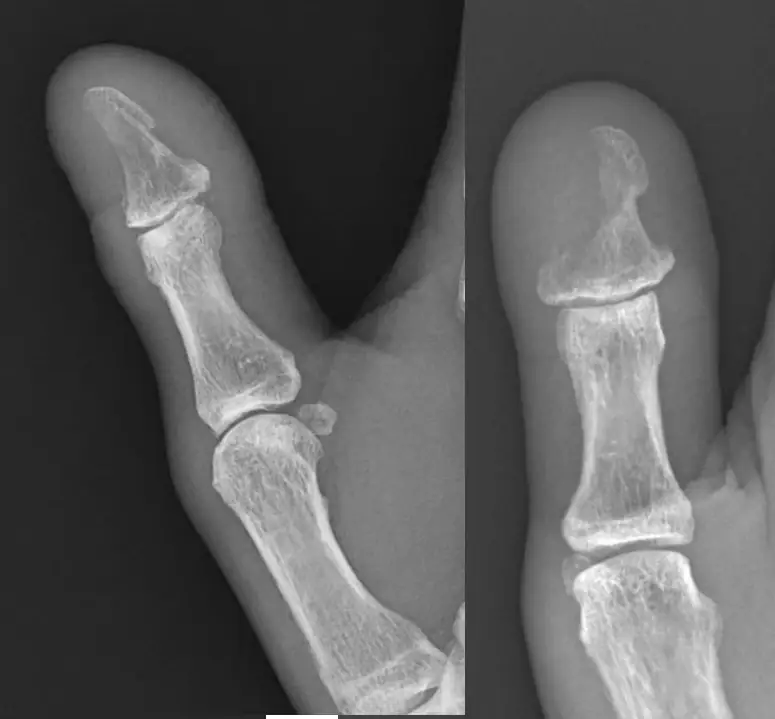

A 64-year-old female presents to urgent care complaining of right thumb pain. The patient states she removed a wooden splinter from her thumb herself about 2 weeks prior, she denies any other trauma or systemic symptoms. ย The patient has a history of Type II diabetes and her last A1C 2 months prior was 9.3.

Physical examination reveals the patient is afebrile with normal vital signs. There is a small, scabbed wound on the palmar surface of the thumb and moderate tenderness, induration, edema and erythema are noted surrounding the wound. There is a faint linear extension of erythema up to the metcarpophalangeal joint. She has decreased interphalangeal joint range of motion. Sensation is intact and capillary refill is brisk. ย ย Radiographs are ordered.

View the x-ray images taken and consider what your diagnosis and next steps would be. Resolution of the case is described on the next page.